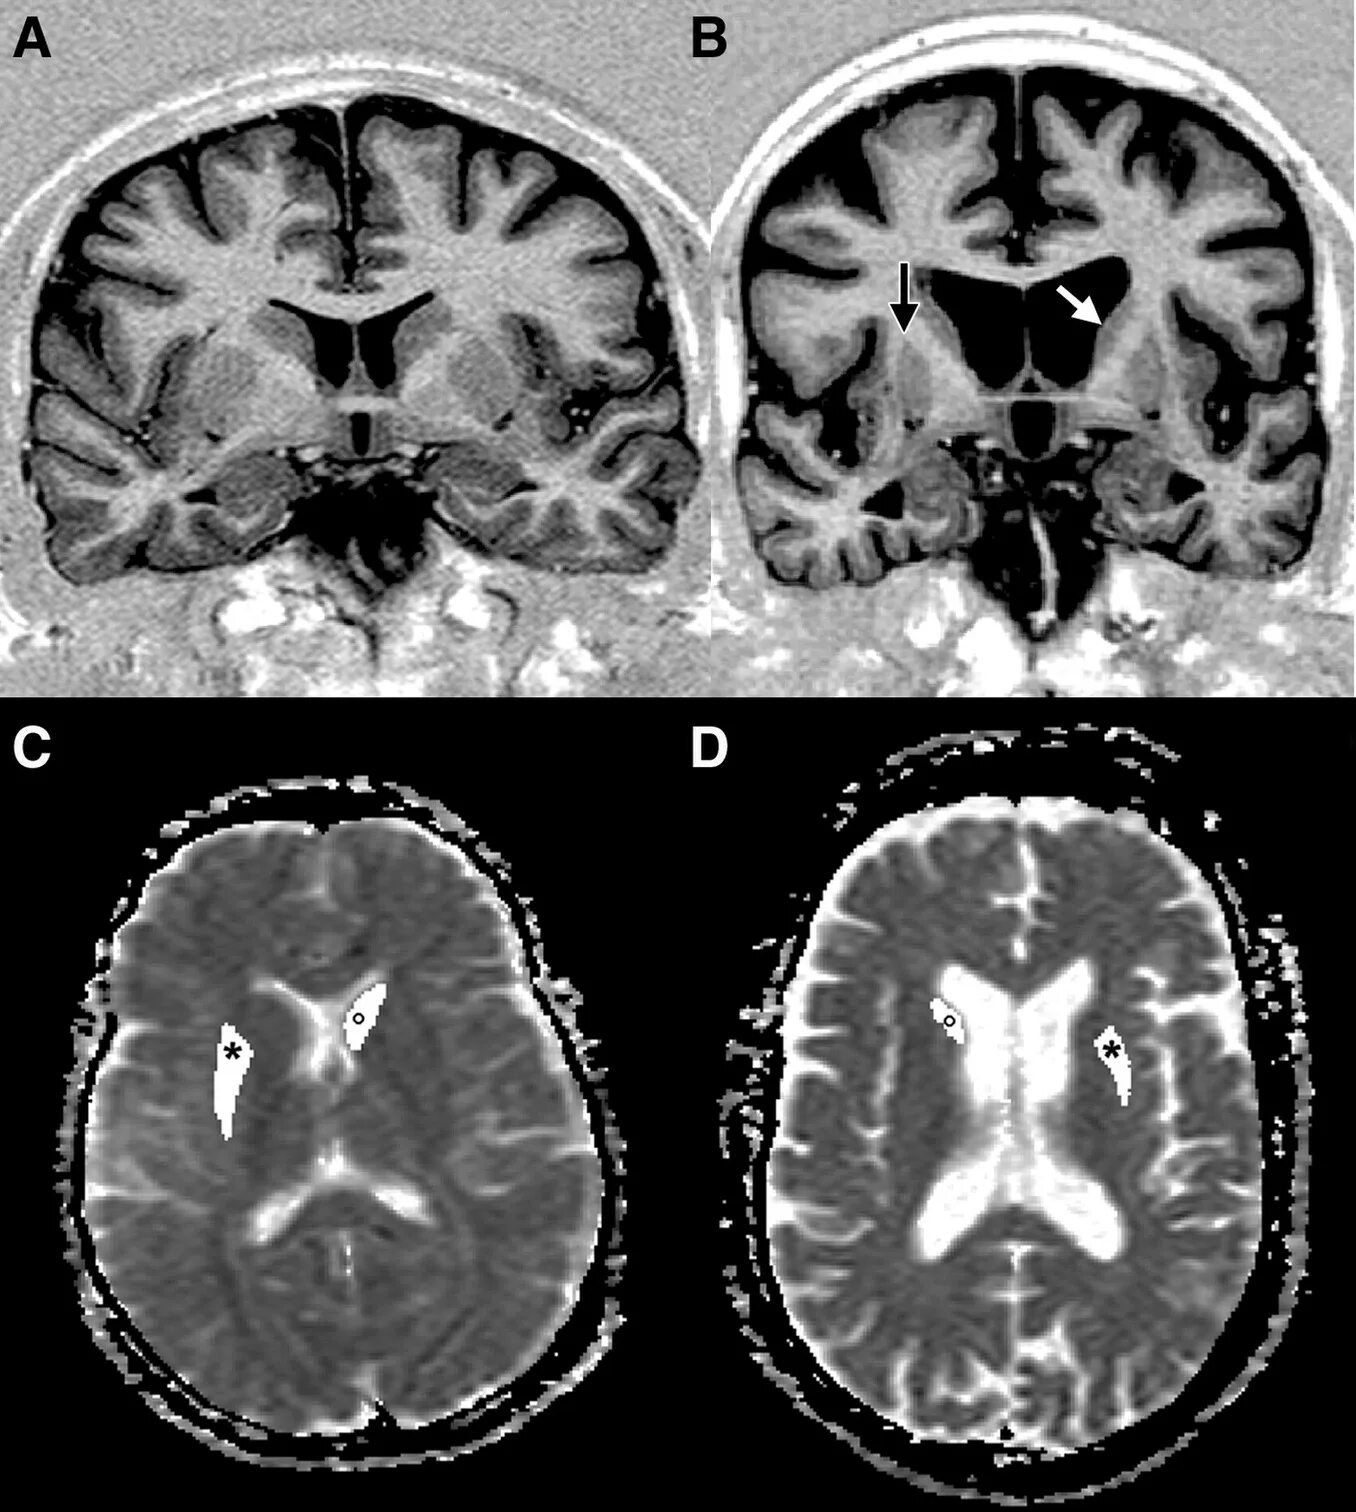

Хорея хантингтона